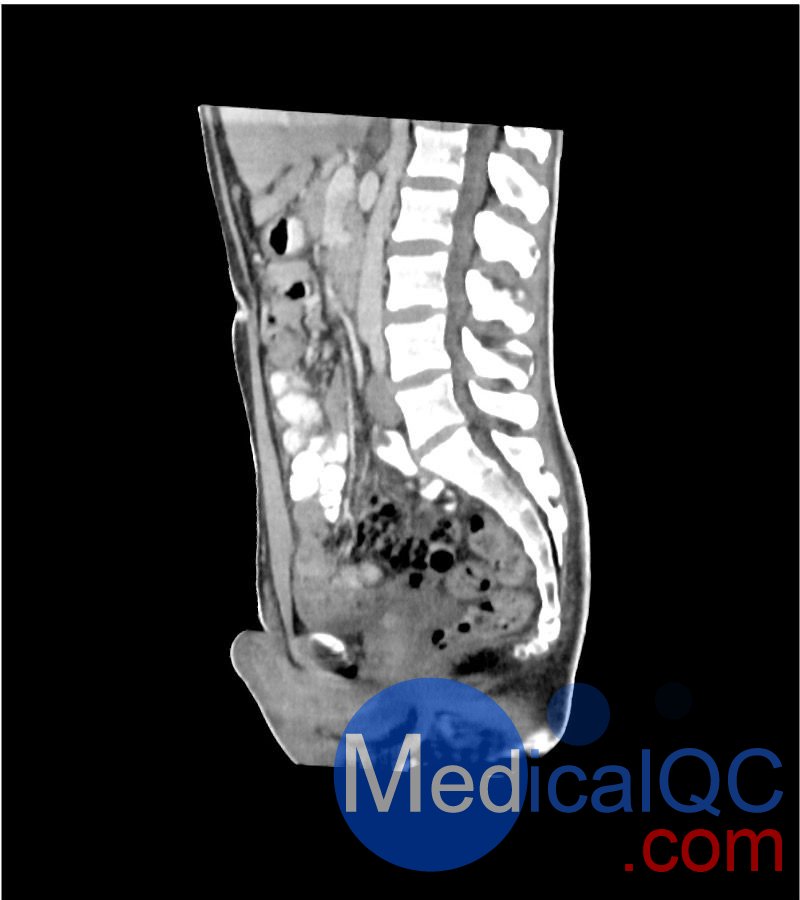

WEK-5501男性腹部模體,WEK-5501男性骨盤模體可模擬門靜脈期的腹部和盆腔增強掃描效果,掃描范圍覆蓋第一腰椎至?xí)巺^(qū)域。

WEK-5501男性腹部模體,WEK-5501男性骨盤模體能對軟組織和骨組織進行細致且逼真的模擬,其內(nèi)部含氣空腔填充有纖維素 - 聚合物復(fù)合材料,該材料的 CT 值約為 - 160 亨氏單位(HU)。

1. 可對脈管系統(tǒng)、骨骼及軟組織進行逼真模擬,涵蓋的器官包括肝臟、膽囊、胰腺、脾臟、腎上腺、腎臟、胃、小腸、結(jié)腸、膀胱及前列腺。

WEK-5501男性腹部模體,WEK-5501男性骨盤模體成像效果圖: